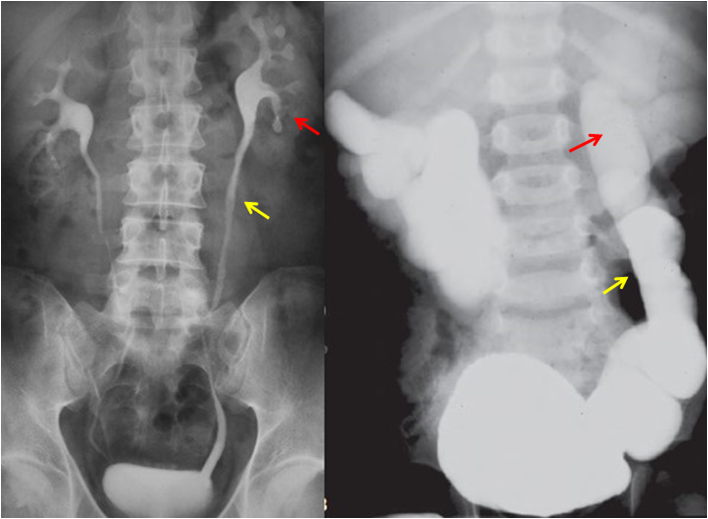

Рисунок слева: нормальный снимок почек (красная стрелка) и мочеточников (желтая стрелка).  Рисунок справа: катастрофические изменения при клапане уретры. Расширение почек и мочеточников (красная и желтая стрелка)

И теперь еще раз взгляните на снимки.

На рисунке справа расширение мочеточников и почек говорит о том, что моча не может адекватно выводиться из-за препятствия. Расширение - высокое давление в мочевыводящих путях. Почкам очень плохо.